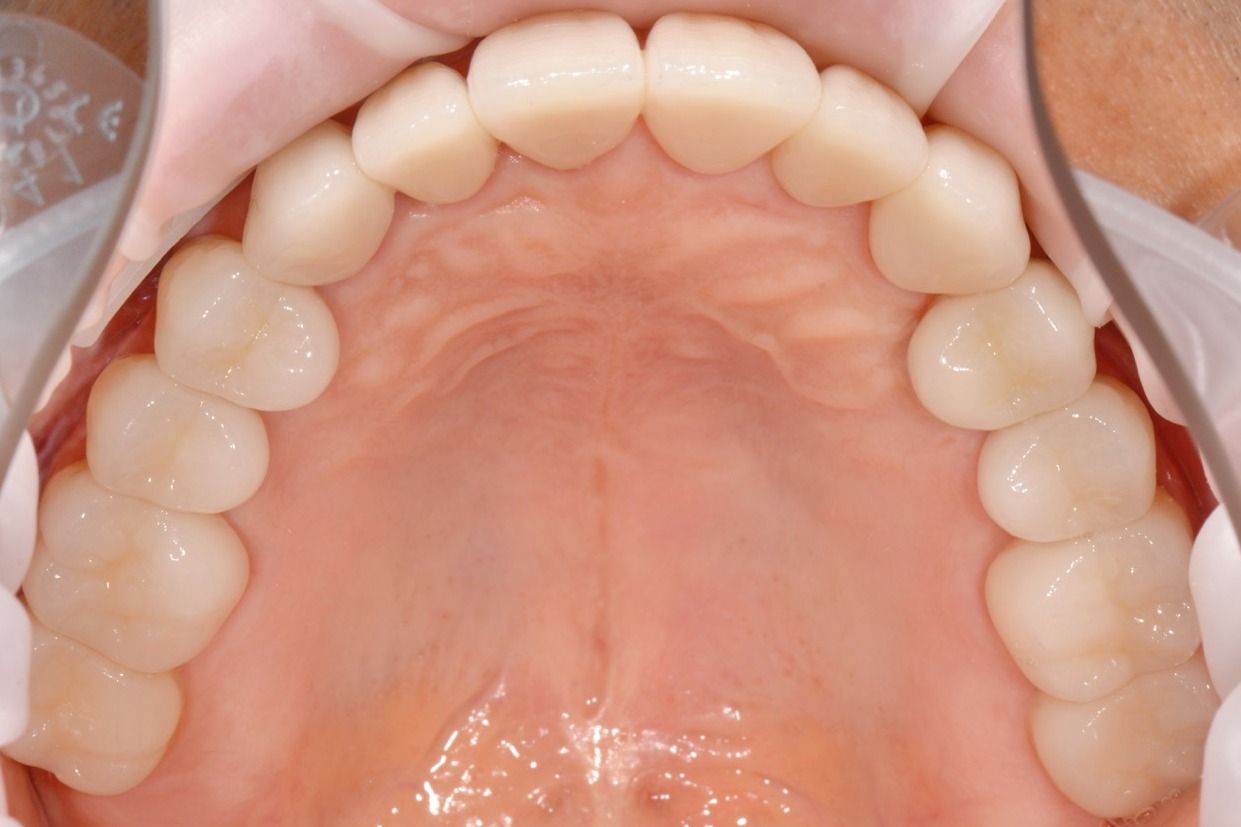

Фотопротокол - это стандарт качественной стоматологии

Фотодокументация

Отснимем и предоставим Вам фотографии двух челюстей

На первичной консультации во время беседы мы выясняем проблемы, запросы и пожелания пациента. В обязательном порядке после осмотра проводим диагностику, чтобы получить всю необходимую информацию о состоянии зубов. Мы составляем фотопротокол. Фотографии позволяют детально изучить проблемные зоны, а пациенту – наглядно увидеть проблемы. В дальнейшем можно легко оценить результаты до и после.